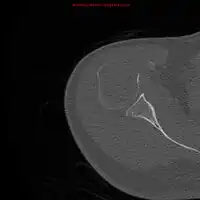

| Solitary plasmacytoma in the long bone of the upper arm | |

1.a. X-ray: solitary plasmacytoma upper arm near shoulder

1.a. X-ray: solitary plasmacytoma upper arm near shoulder 1.b. CT scan: solitary plasmacytoma upper arm near shoulder